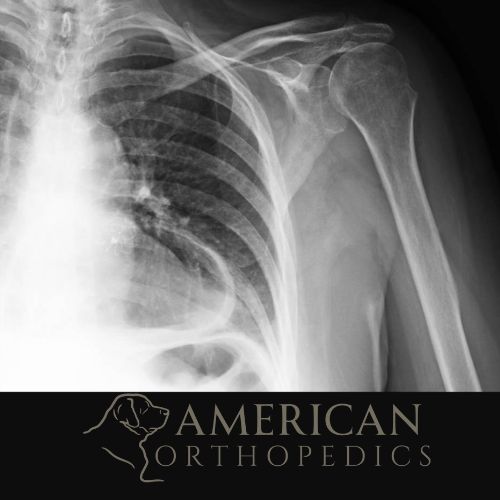

Reverse Total Shoulder for Rotator Cuff Arthropathy

Patient of Dr. Ratner.

Before

Reverse Total Shoulder for Rotator Cuff Arthropathy before - Drew Ratner MD Orthopedic Surgeon 1